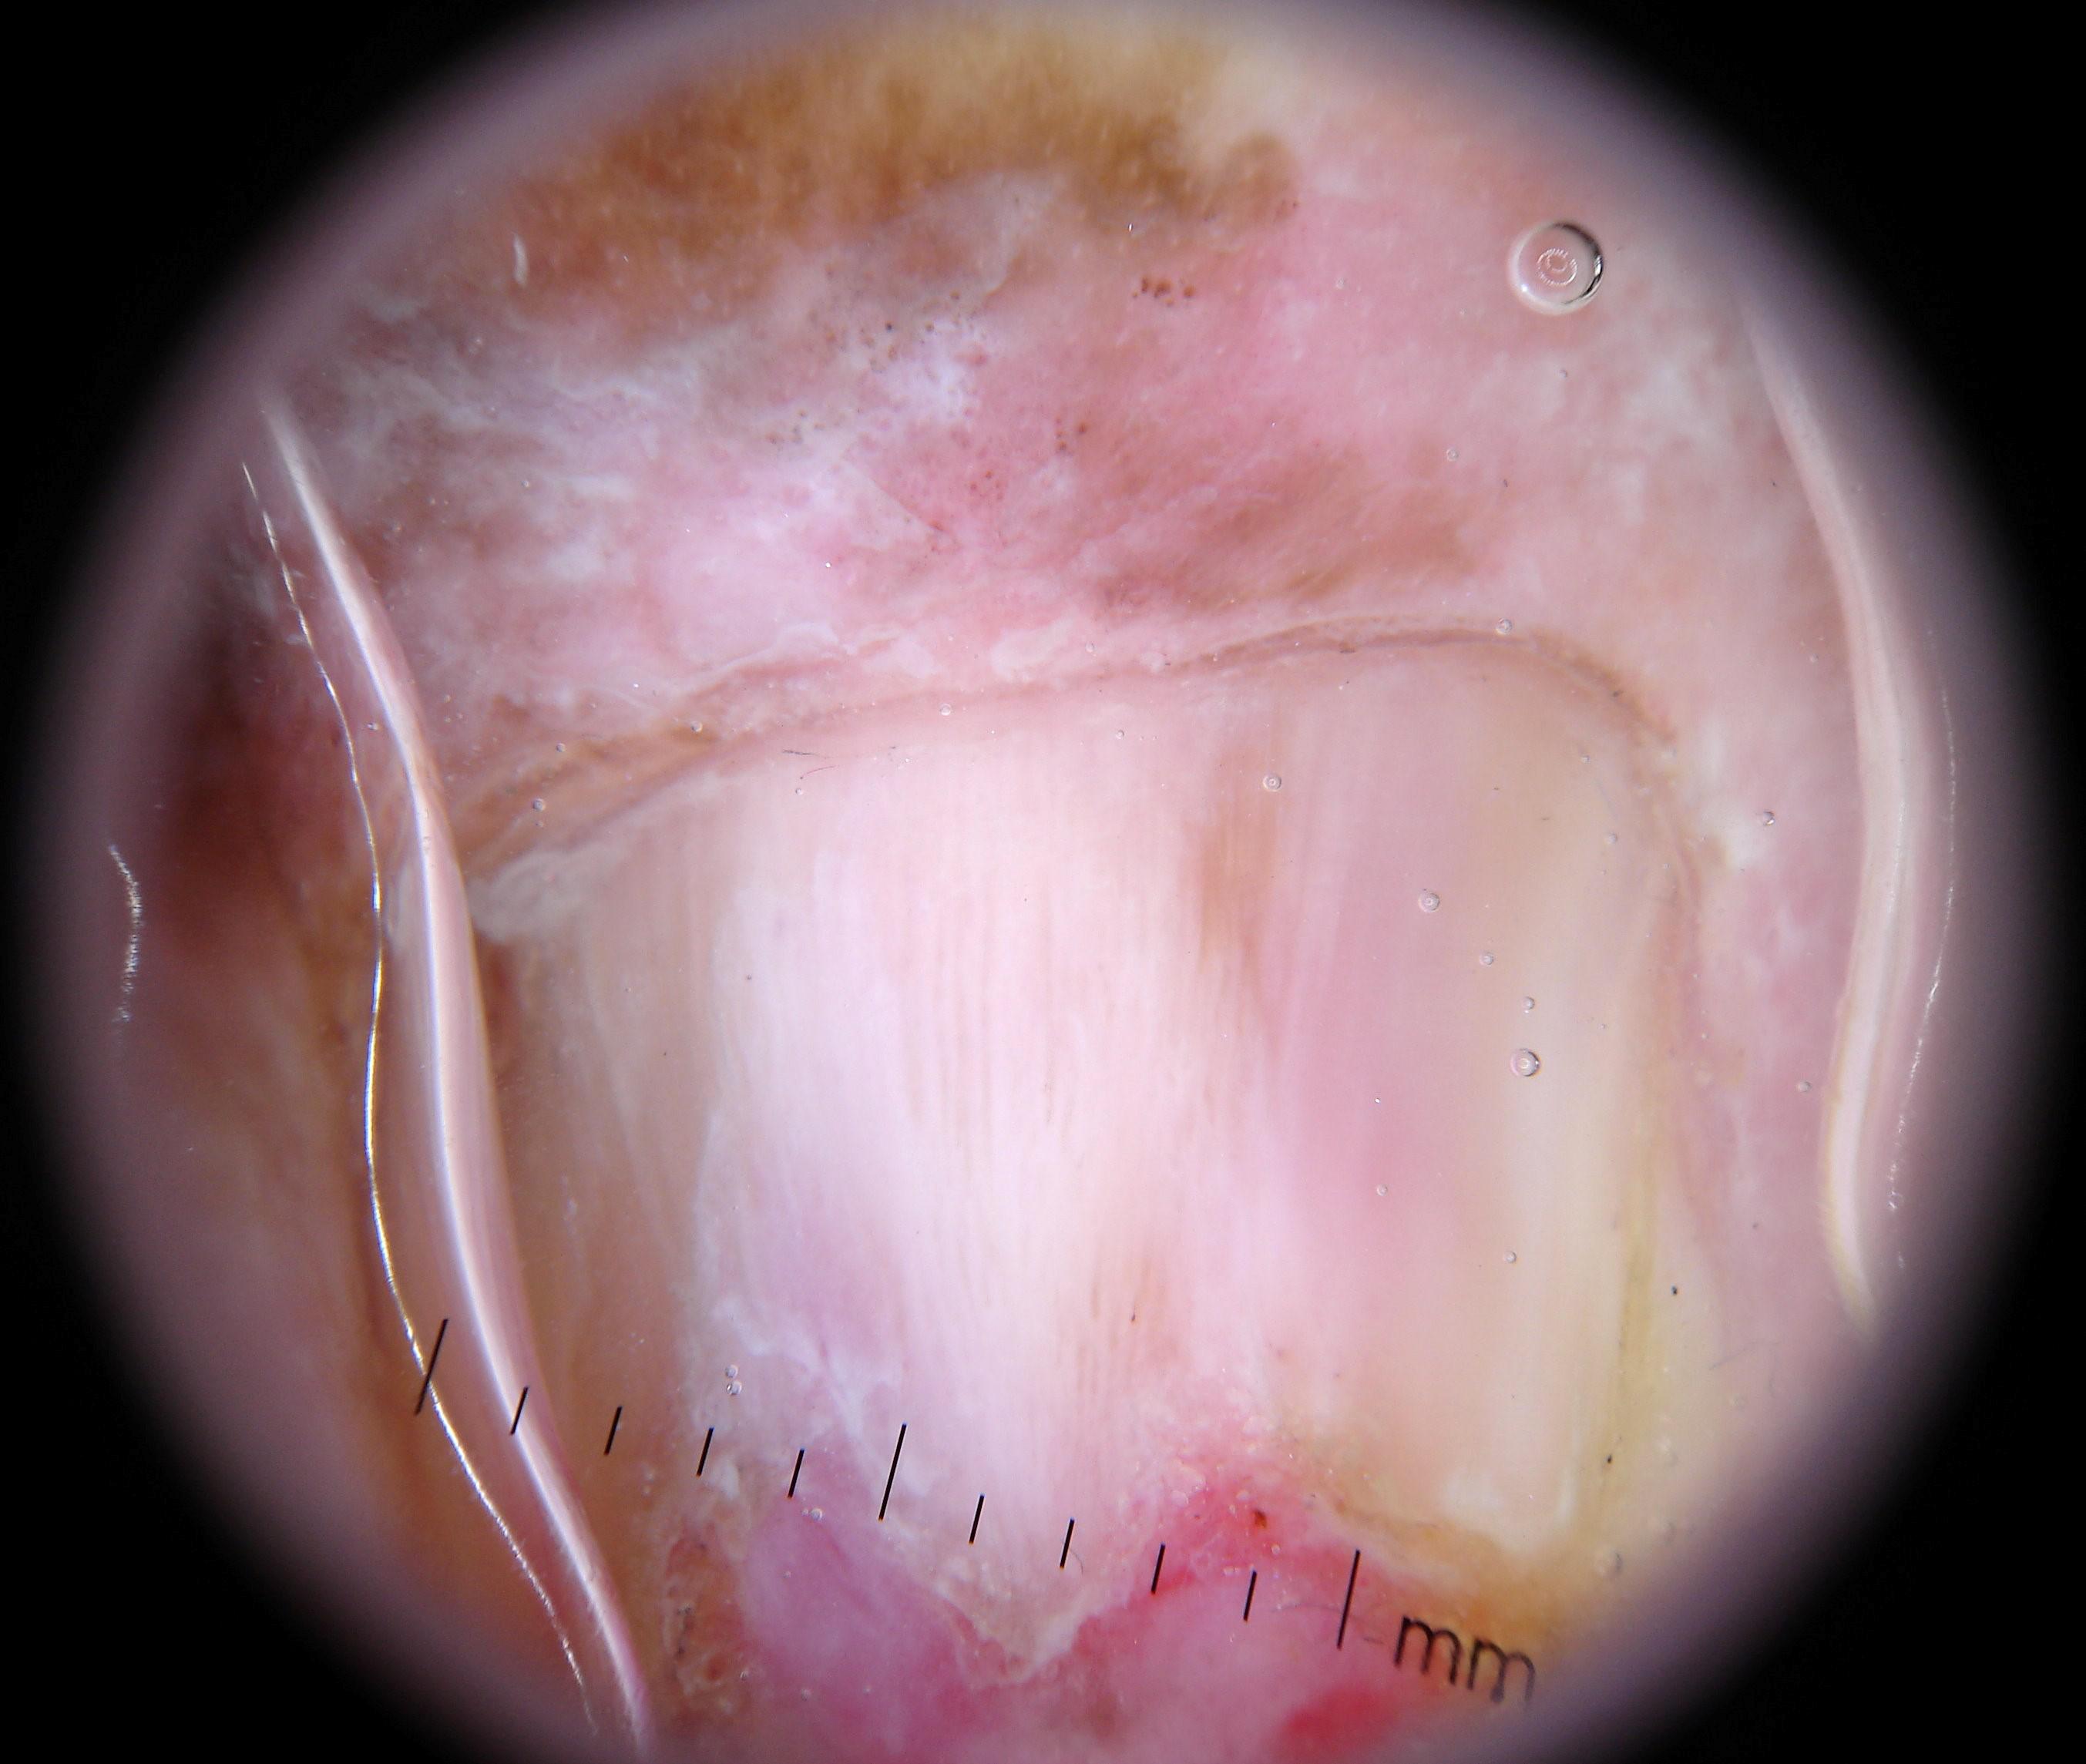

{

"age_approx": 65,

"anatom_site_general": "upper extremity",

"anatom_site_special": "acral NOS",

"concomitant_biopsy": true,

"dermoscopic_type": "contact polarized",

"diagnosis_1": "Malignant",

"diagnosis_2": "Malignant melanocytic proliferations (Melanoma)",

"diagnosis_3": "Melanoma in situ",

"diagnosis_confirm_type": "histopathology",

"family_hx_mm": false,

"image_type": "dermoscopic",

"mel_thick_mm": "0.00",

"melanocytic": true,

"patient_id": "IP_3069248",

"personal_hx_mm": false,

"sex": "male"